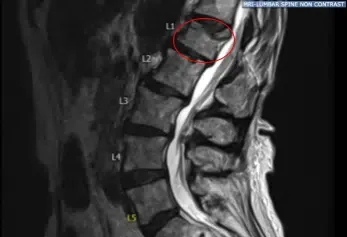

La resonancia preoperatoria mostró un cambio hiperintenso de la señal STIR en la vértebra L1. Tras una extensa discusión y el fallo en el manejo no quirúrgico, fueron llevados al quirófano para un procedimiento de cifoplastia L1 para controlar el dolor.